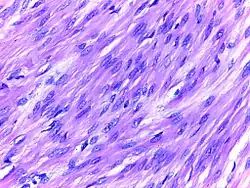

Leiomyoma uterus | Micrograph of leiomyoma uterus showing bundles of smooth muscle cells of uniform size and shape. The cells are spindle shaped with oval nucleus. | Category: Histopathology of uterine fibroids | Leiomyoma |